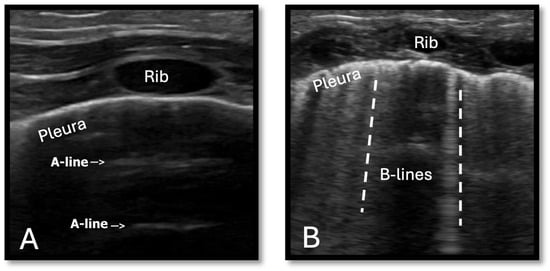

3.2. Monitoring Pulmonary Overcirculation